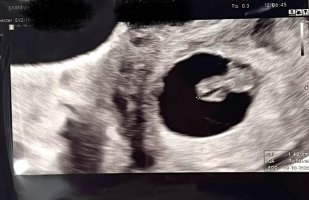

Ultralydbilder ✨